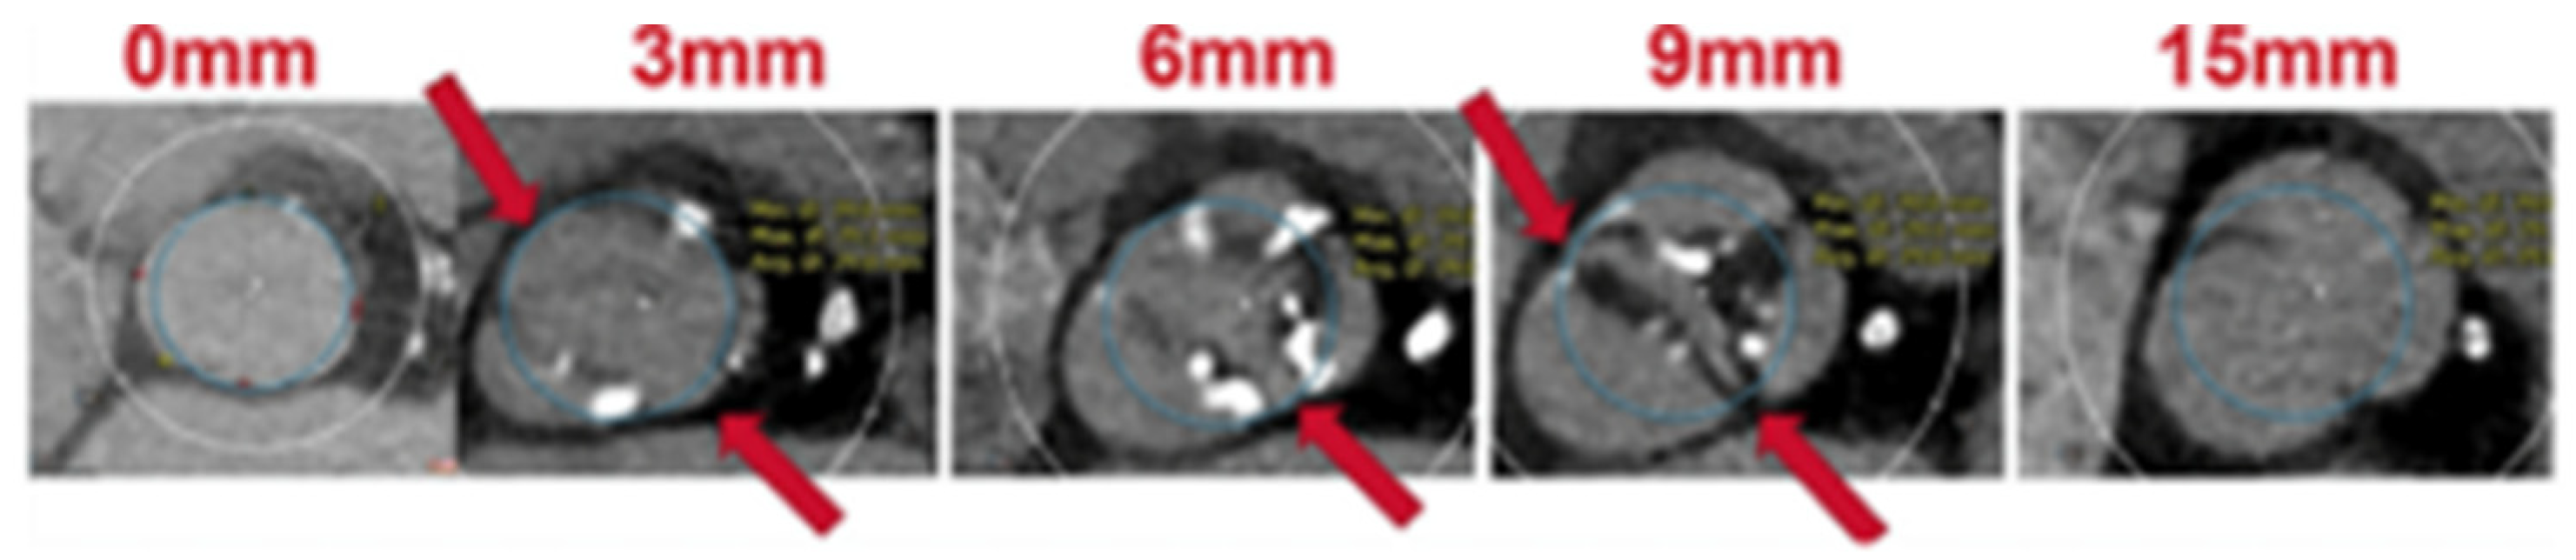

- Iannopollo, G.; Romano, V.; Buzzatti, N.; Ancona, M.; Ferri, L.; Russo, F.; Bellini, B.; Granada, J.F.; Chieffo, A.; Montorfano, M. Supra-annular sizing of transcatheter aortic valve prostheses in raphe-type bicuspid aortic valve disease: The LIRA method. Int. J. Cardiol. 2020, 317, 144–151. [Google Scholar] [CrossRef] [PubMed]

- Iannopollo, G.; Romano, V.; Esposito, A.; Guazzoni, G.; Ancona, M.; Ferri, L.; Russo, F.; Bellini, B.; Buzzatti, N.; Curio, J.; et al. Update on supra-annular sizing of transcatheter aortic valve prostheses in raphe-type bicuspid aortic valve disease according to the LIRA method. Eur. Heart J. Suppl. 2022, 24, C233–C242. [Google Scholar] [CrossRef]